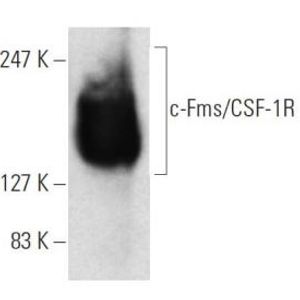

JUL 28, 2025Drug Discovery & DevelopmentOne lab technique that has been around since what feels like the dawn of time is Western blotting, and it doesn&r ...